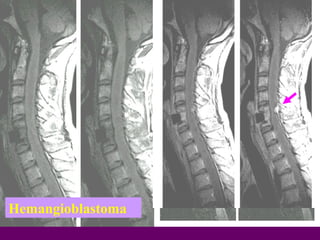

Hemangioblastoma